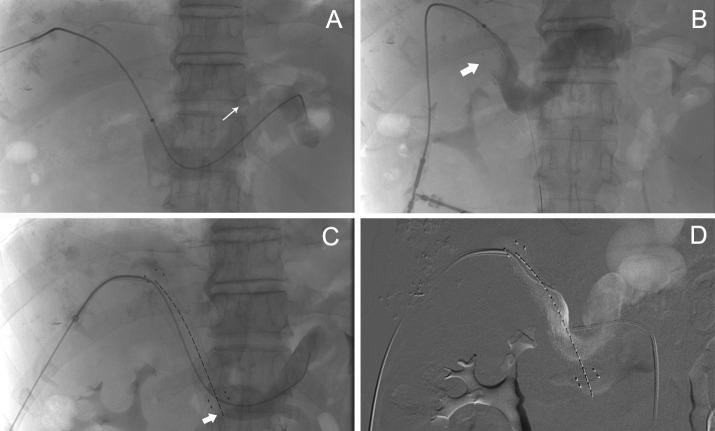

From 2016 to 2018, 68 patients diagnosed with malignant obstruction in the porta hepatis were retrospectively included in this study. Twenty-eight patients (group A) received stent placement with iodine-125 seed-strand implantation, and 40 patients (group B) received stent placement only. All patients underwent numerous transarterial chemoembolizations (TACE) after stent implantation. All patients were followed up until death. Clinical data, stent patency and survival time were recorded for further analysis.

There was no significant difference between the two groups in terms of length of malignant obstruction and baseline characteristics. 68 stents were successfully implanted in both groups.Iodine-125 seed strands were successfully deployed and completely covered the length of the stent in group A. Liver function and jaundice improved continuously in the first 9 months after treatment (P<0.05). Compared to group B, the mean stent patency time was significantly longer in group A (5.5 ± 2.09 months versus 6.86 ± 1.82 months, P<0.001). The mean survival time is longer in group A than in patients in group B (10.03 ± 3.04 months VS 7 ± 2.44 months, P<0.001).

ILBT in combination with stent implantation and TACE has proven to be a feasible and effective palliative treatment to maintain stent patency in patients with PVTT and MOJ.